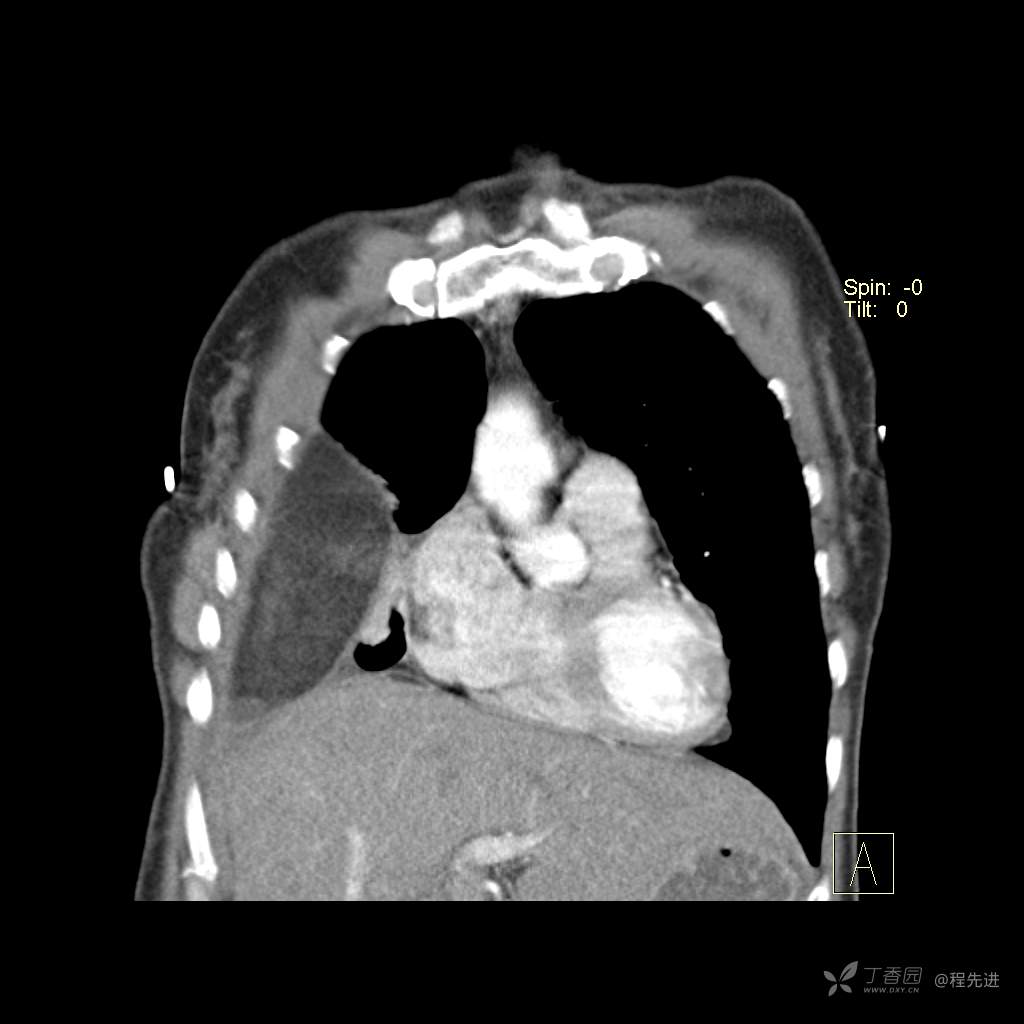

患者性别:女

患者年龄:51岁

简要病史:胸闷半年